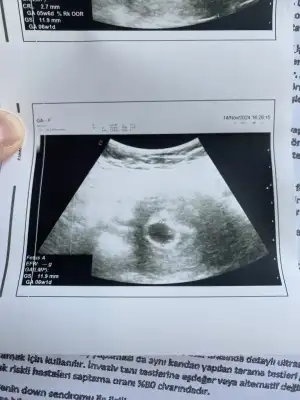

Yine asistan yaptı ultrasonu. Biraz zorlandı. Derin nefes alma diyor bana. Benim kalbim göğüs kafesime sığmıyorki

Tuttum nefesimi. Buldu keseyi. Dr geldi müşahedeye. Kese haftasıyla uyumlu. Bebek de göründü.

Dr yaklaştırdı. Bak şu küçük noktaya deli gibi atıyor. O kalbi dedi. Elhamdülillah

Şimdi sesini dinlemeyeceğiz çünkü çok küçük etkilenmesin dedi. Siz gördükten sonra dinlemeye gerek yok dedim.